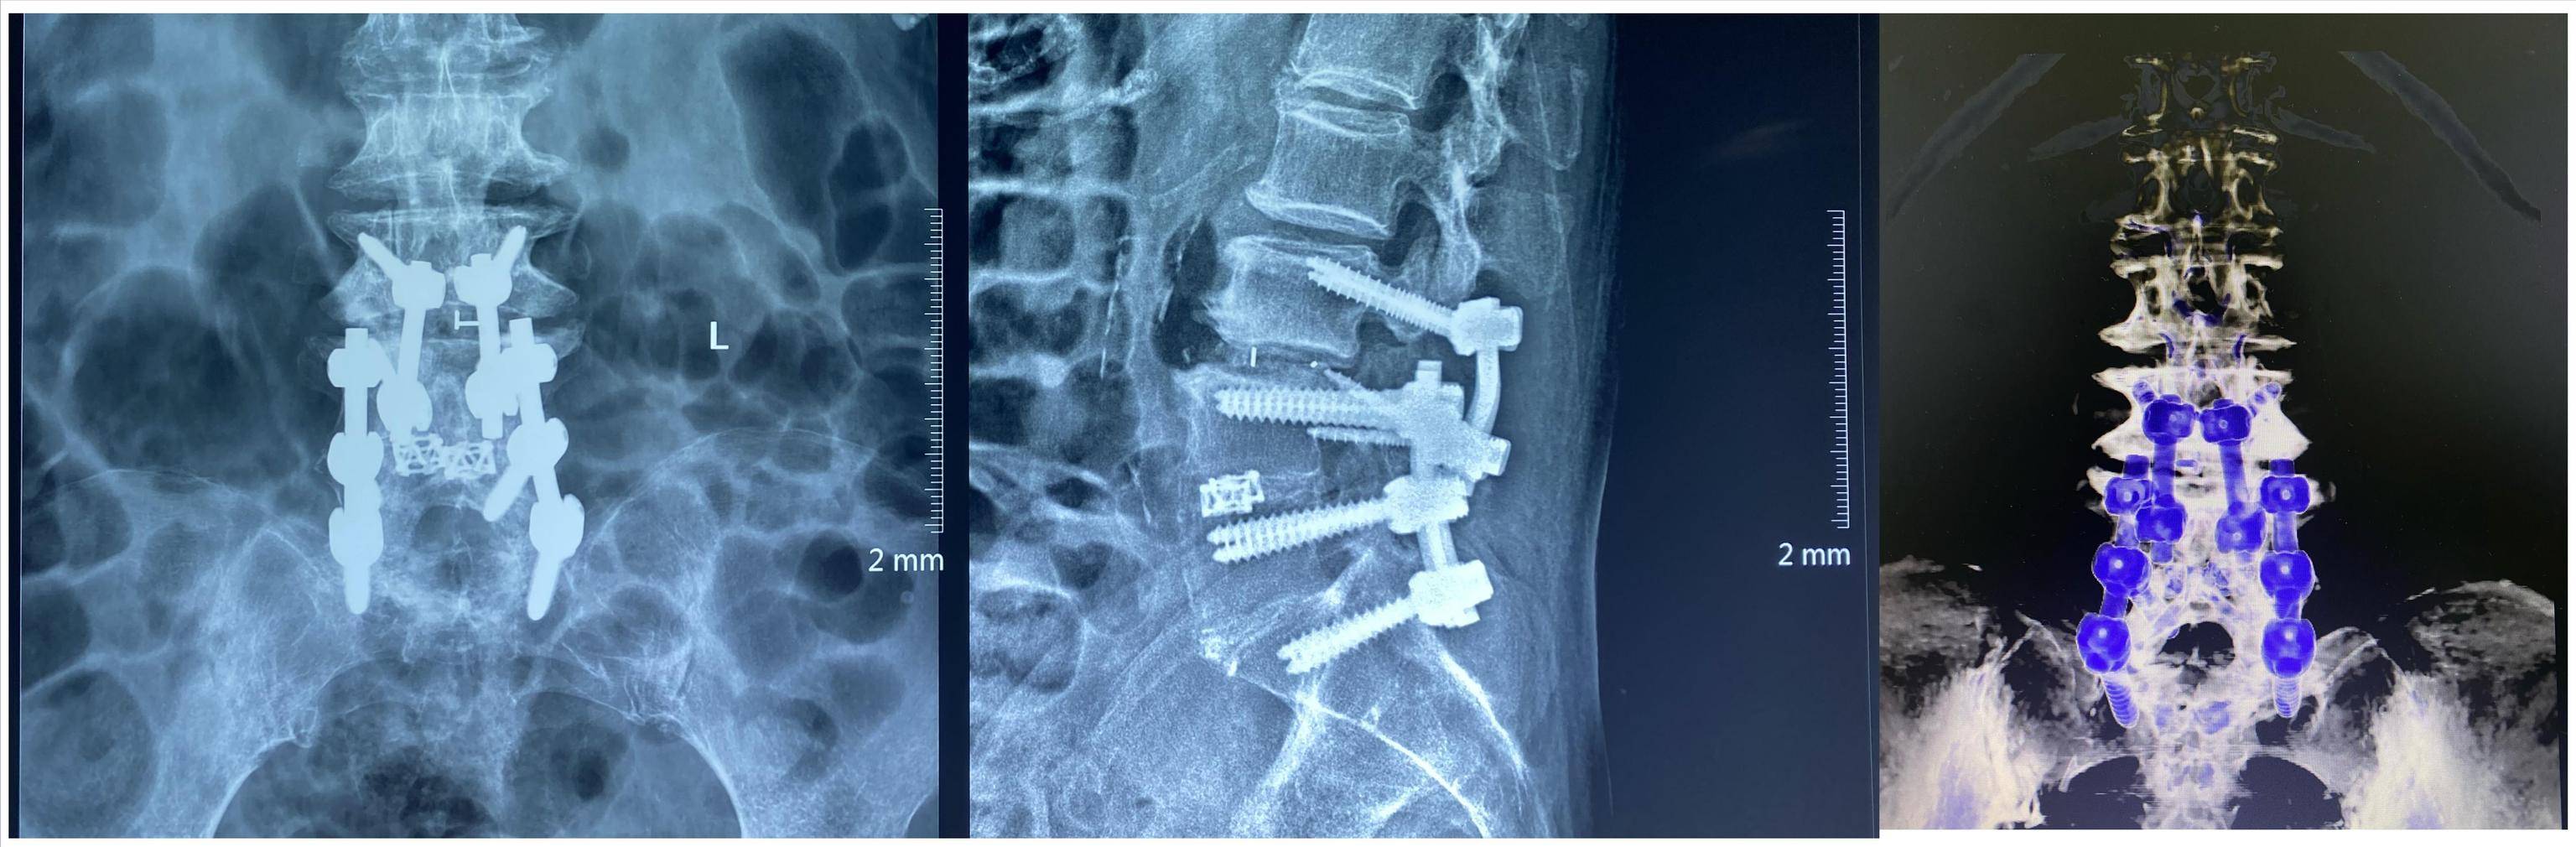

脊柱病医院院长郝定均及腰椎病区主任刘团江一致建议 , 将O-arm与“天玑”骨科手术机器人相结合 , 通过O-arm快速、高效地获取术区影像资料 , 通过“天玑”骨科手术机器人工作站进一步评估术中置钉的可行性并规划钉道 , 最终在“天玑”骨科手术机器人导引下完成钉道的制备 。

术后患者腰腿痛症状明显改善 , 下地行走自如 。

随着人口老年化的来临 , 微创化、精准化、智能化是当下脊柱外科手术发展的方向 。 以皮质骨轨迹螺钉技术(CBT)为代表的微创手术 , 无需剥离显露上位关节突关节 , 一定程度上避免手术邻近节段退变 , 降低了再次手术的风险 。 对于初次手术的高龄患者受限于其较差的骨质 , 不得不通过提升椎弓根钉的直径或采用骨水泥螺钉降低内固定相关并发症 , 再次手术时将会面临更多的挑战 , 皮质骨螺钉可能会发挥其独特的作用 。 通过O型臂360度自动环型扫描取像 , 3D立体影像系统可实现各层面影像的实时、立体重建 。 “天玑”骨科手术机器人系统可基于O-arm抓取的高清图像在术前完成路径规划 。 通过光学示踪完成机器人手臂位置自动补偿 , 保障手术路径与计划路径一致 , 辅助完成钉道的制备 , 避免伤害到周围的神经血管等重要器官组织 , 大大提高手术安全性、减少病患风险及并发症的发生 。

西安市红会医院脊柱病医院一直不断探索拓宽微创脊柱外科手术治疗方式 。 CBT是微创脊柱外科的代表性技术 , O-arm及“天玑”手术机器人是精准医疗、智慧医疗时代的中坚力量 , 将O-arm及“天玑”手术机器人结合使用 , 辅助完成CBT螺钉的置入属于西北首次 , 该方法不但兼顾手术的安全性及有效性 , 还能让高龄老人的腰椎翻修手术有了更加微创可靠、精准智能的选择 。